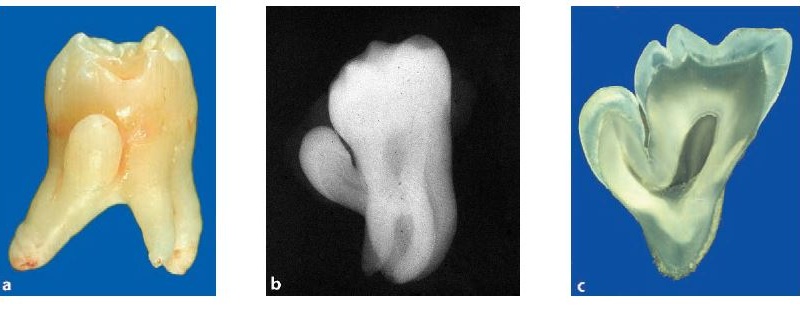

amelogenesis imperfecta

Amelogenesis Imperfecta

– Pärilikud arenguhäired emaili või hambaluu ehituses on haruldased ning on näha nii piimakui ka jäävhammastes.